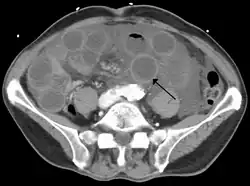

| Computed tomography (CT) showing dilated loops of small bowel with thickened walls (black arrow), findings characteristic of ischemic bowel due to thrombosis of the superior mesenteric vein. | |